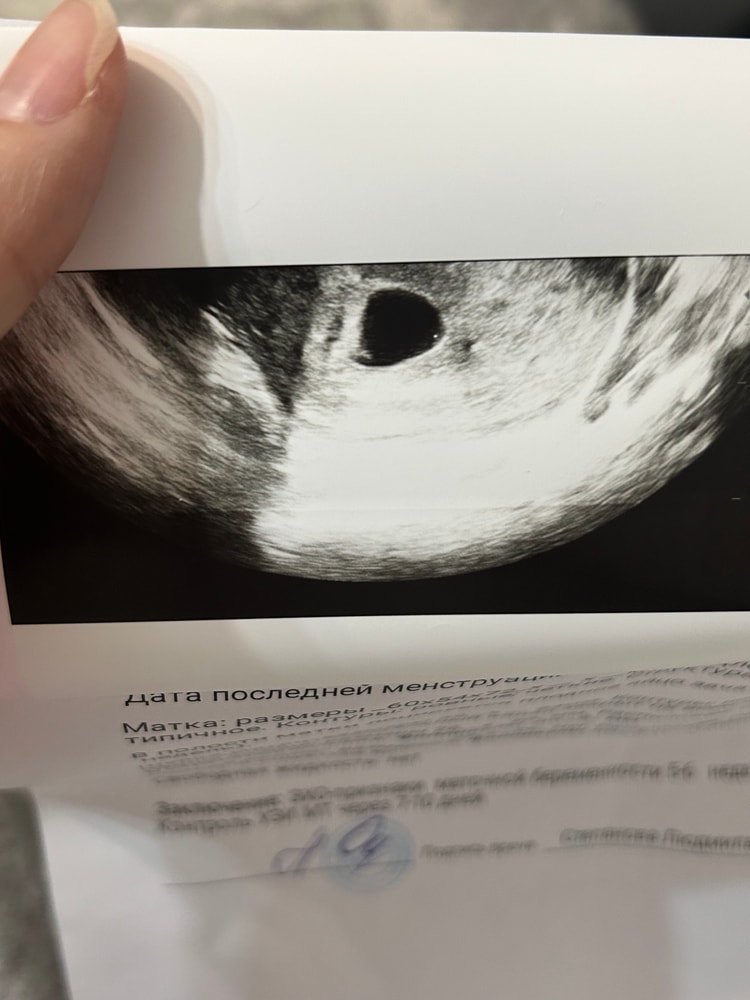

УЗИ 5 недель

Душевные переживанияделала вчера узи, хгч 15к+, но сказали что эмбрион слишком маленький, сравнила с разными узи из интернета и напряглась..всю ночь думала о том разрастется ли, ведь должен уже в 5 и 4 быть больше, нет?

Какие размеры эмбриона? У меня с младшим сыном на сроке 5,5 нед хгч был 15700, эмбрион был 1,8 мм + сердцебиение

Ну его и не должно быть в 5,4 недели,это рано,а хгч разный может быть,у меня тоже высокий был на 23 дпо -14755,а 23 дпо это срок 5,2 всего,просто хгч рос быстро,но эмбрион от этого раньше не появился,а вот в 6,3 недели (31 дпо) был уже 5,4 мм с сб пя 19 мм было

Эмбрион появляется на УЗИ после ХГЧ 17000. И то не факт, потому что ХГЧ - это в основном показатель роста плодного яйца